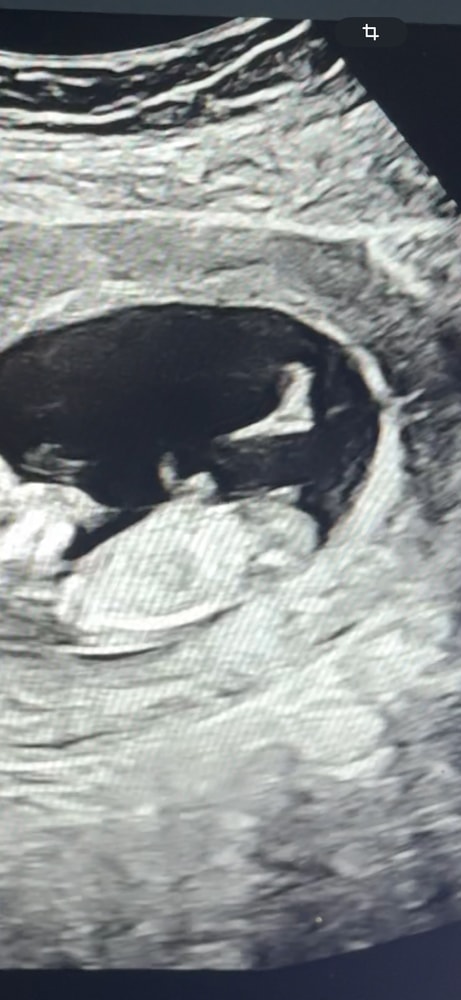

Пол малышаХочу продолжить тему Пола, вот фотка с сыном. Тут в 11 недель сразу определили что мальчик, ну оно и понятно)

первое фото - сынок старший